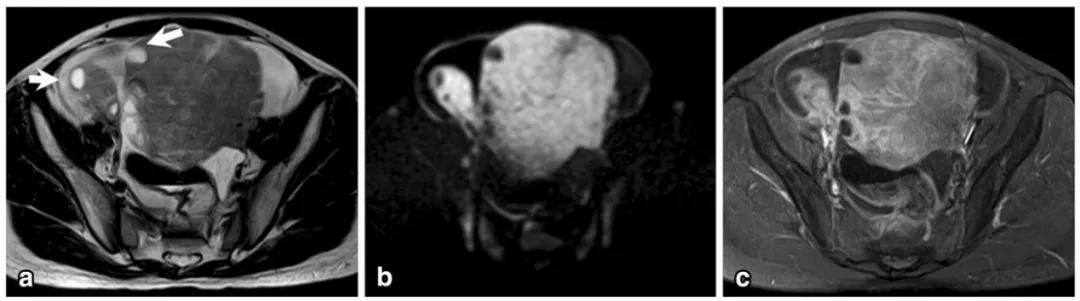

女,12 岁,卵巢 Burkitt 淋巴瘤。双侧卵巢肿物,T2WI 信号稍高(图 a),DWI 呈高信号(图 b),增强扫描明显强化(图 c),箭头显示肿物边缘多发囊性结节,为卵泡保留征。